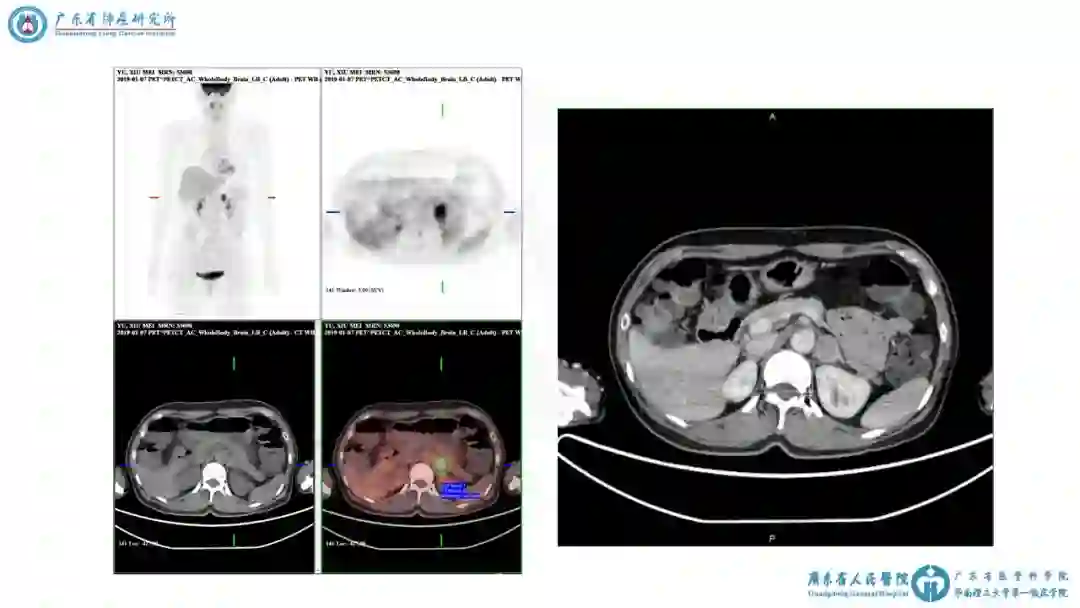

患者病史:2019-01-04 入院

入院完善血常规、肝肾功能等检查未见显著异常 。肿瘤指标未见异常。肺通气功能及心脏B超未见显著异常。

入院后予拜新同30mg qd控制血压,血压波动于120~140/70~90mmHg。

图表资料

讨论要点2:多结节的寡转移?

1)患者目前诊断与分期

① 患者双肺多发病变是否为同时多原发癌?

② 患者肾上腺病灶是否为寡转移癌?

科内意见

① 双侧多原发肺癌伴左侧肾上腺转移,cT1b(m)N0M1b,IVa期。

② 高血压病。